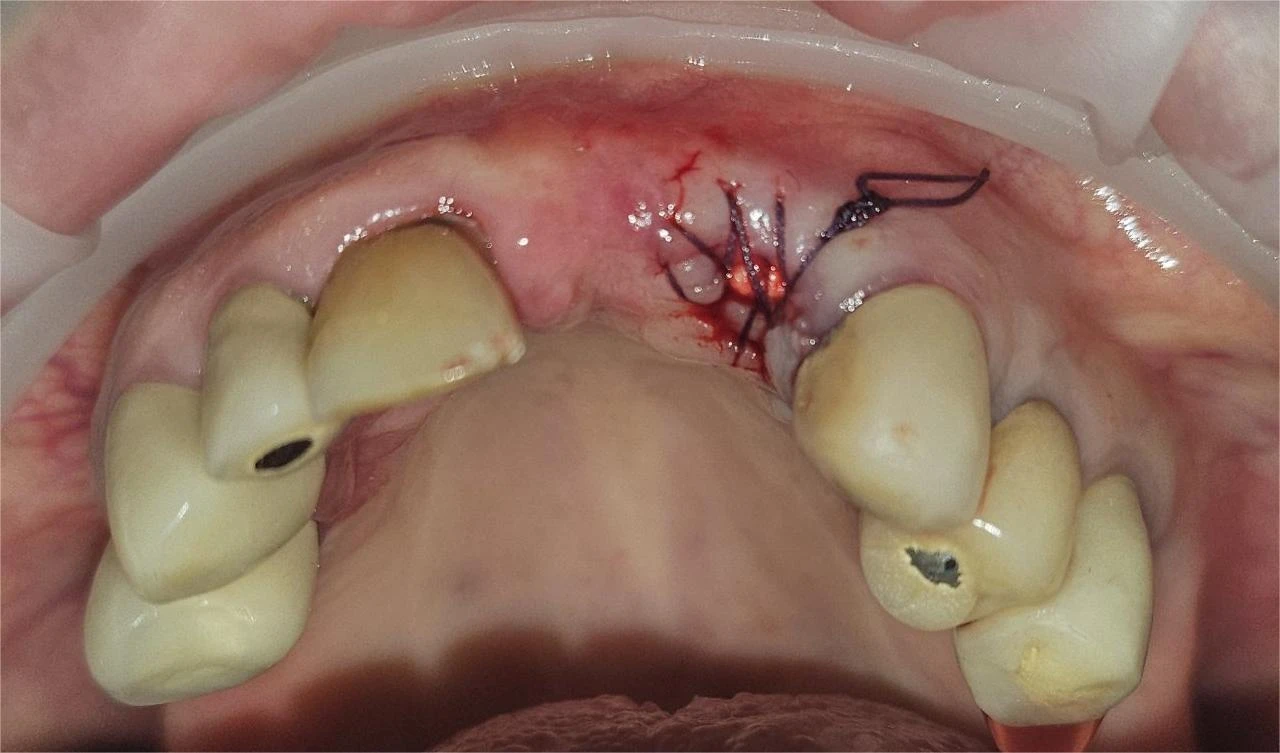

Поставяне на костно вещество

След екстракцията (изаждането) на зъб/и, които не са с възпалителни процеси се поставя лиофилизирана и стерилизирана говежда кост, с цел укрепване, изграждане и запазване на обема на коста и меката тъкан, при последващо протезипане с мостова конструкция или имплант с корона.

При всички изброени хирургични манипулации се поставя местна упойка и екстракционата рана се зашива. Конците се свалят  до 10-14 дни. При някои състояния се налага предписване  на антибиотична защита или антииотично лечение.